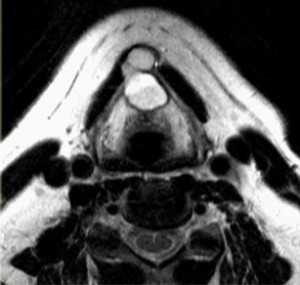

(Слева) МРТ Т1ВИ FS с КУ, аксиальная проекция. Крупная шваннома в нижней части шеи справа, которая лежит на средней лестничной мышце. Отмечается неравномерное накопление контраста по периферии опухоли. Центральная область, не накапливающая контраст, представляет собой участок кистозной дегенерации. При поражении нижних шейных лимфоузлов патологический очаг обычно расположен медиальнее, возле внутренней яремной вены.

(Справа) MPT Т2ВИ, аксиальная проекция. В нижней части шеи визуализируется шваннома сигнал гетерогенный гиперинтенсивный. Опухоль, расположенная в паравертебральном пространстве, раздвигает и деформирует переднюю и среднюю лестничные мышцы.